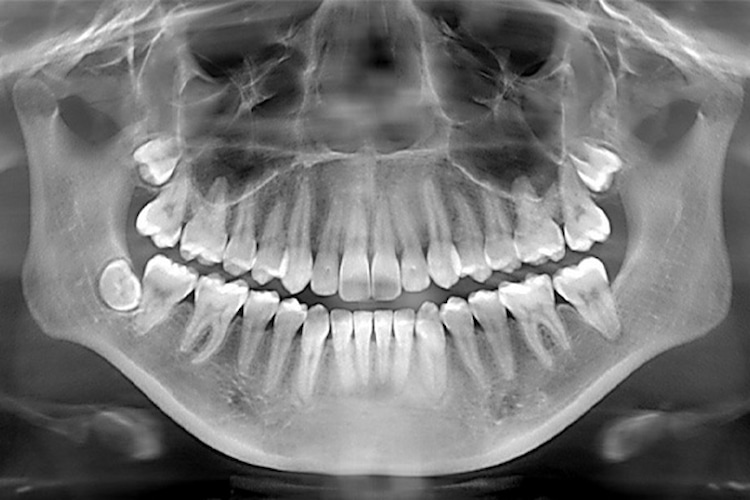

- Panoramic X-ray: This type of X-ray takes a wide-shot picture of your entire mouth! It captures all your teeth in both jaws, the jawbone, and even the sinuses. It’s helpful for getting a general overview of your mouth, checking wisdom teeth development, and planning orthodontic treatment (braces).

The final X-ray image, whether on film or digital, appears in shades of gray. Denser areas, like your teeth and jawbone, show up lighter because they block more of the X-rays. Less dense areas, like your gums or air pockets, appear darker because they allow more X-rays to pass through. By analyzing these variations in gray, your dentist can identify problems. For instance, a cavity might appear dark because it doesn’t block X-rays well, and areas of bone loss might also appear darker due to less dense bone being present.